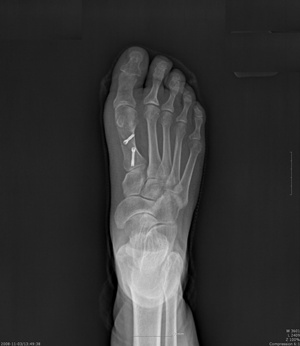

무지외반증은 무지(엄지발가락)가 바깥쪽으로 휘어지는 것(외반)을 말하는 질환명이다.

엄지발가락이 두 번째 발가락 쪽으로 휘어지면서 엄지발가락 관절부위가 돌출되고 2차적으로는 발바닥에 굳은살이 생기게 된다. 진행되면서 부종과 통증이 동반된다.

서울 나누리병원 윤재영 부장은 “걸을 때 엄지발가락과 엄지발가락 둘째 발가락을 밀면서 통증이 유발되고, 비정상적인 보행으로 무릎이나 허리까지 스트레스를 유발하여 관절통까지 생기게 되는데 보통 15∼20도 이상 휘어졌을 경우 무지외반증이 심하게 진행된 상황이고, 30도 이상이면 바로 수술적인 치료가 필요한 상황이다”고 경고했다.

무지외반증은 증상이 심하지 않을 경우 통증을 줄이기 위해 진통제와 함께 보조기, 특수 교정 신발을 사용하게 된다. 하지만 발가락이 35도 이상 휘면 엄지발가락과 인대를 바로 잡아 주는 절골술을 통해 치료하게 된다. 튀어나온 엄지발가락 뼈 일부를 절단하여 똑바로 고정한 뒤 핀을 박아 정상적인 형태로 만들어주는 수술이다.

무지외반증 수술은 뼈를 수술하지만 실제로는 간단한 수술이다. 최근에는 3∼5cm만 절개하는 최소 절개 수술법과 녹는 봉합사를 이용해 흉터 최소화도 가능하다. 수술 후에도 3∼4cm의 작은 흉터만 남으며 그마저도 시간이 지나면서 사라져 흉터에 대한 환자들의 부담감을 최소화했다.

또한 수술은 발목 국소마취로 30∼40분 정도 진행되며, 회복이 빨라 2, 3일 만에 퇴원하게 되며 핀은 수술 후 6주 후에 제거하고 그 이후에는 걷는데 어려움을 겪지 않을 정도로 좋아진다. /생활경제팀 osenlife@osen.co.kr